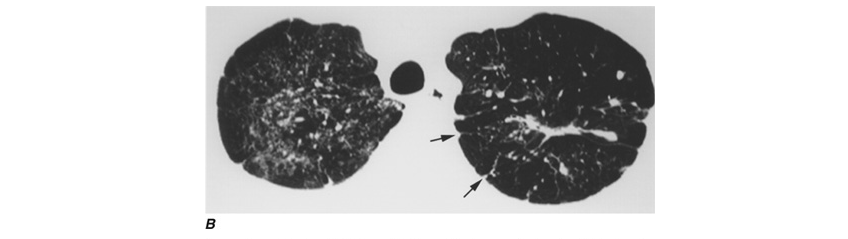

Epidemiologic studies have consistently shown associations between exposure to biomass smoke and both chronic bronchitis and COPD, with odds ratios ranging between 3 and 10 and increasing with longer exposures. In addition to the common occupational exposure to biomass smoke of women in developing countries, men from such countries may be occupationally exposed. Because of increased migration to the United States from developing countries, clinicians need to be aware of the chronic respiratory effects of exposure to biomass smoke, which can include interstitial lung disease (Fig. H-4). Evidence is beginning to emerge that improved stoves with chimneys can reduce biomass smoke–induced respiratory illness in both children and women.